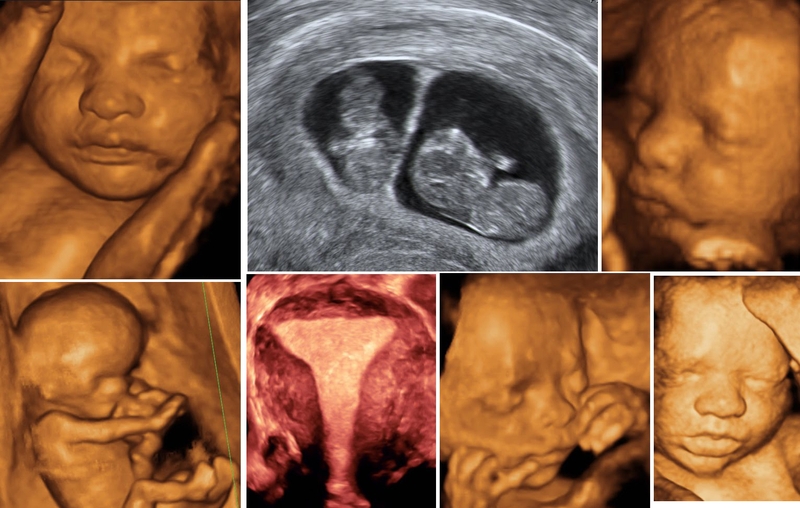

Siêu âm là phương pháp chẩn đoán hình ảnh không xâm lấn, trong đó sử dụng sóng siêu âm với tần số cao để dựng lại hình ảnh giải phẫu của bộ phận cơ thể cần được kiểm tra. Trong quá trình siêu âm, sóng siêu âm sẽ quét và ghi nhận toàn bộ hình ảnh, cấu trúc của bộ phận cần kiểm tra và gửi đến máy siêu âm. Máy siêu âm tiếp nhận thông tin và tạo ra hình ảnh hoặc video chi tiết về bộ phận được siêu âm hoặc hình thái cũng như chuyển động của em bé trong bụng mẹ.

Với phụ nữ mang thai, siêu âm định kỳ theo chỉ định của bác sĩ là việc làm cần thiết. Việc thăm khám và siêu âm thai định kỳ giúp bác sĩ theo dõi được quá trình phát triển của thai nhi. Từ đó, bác sĩ sẽ sớm phát hiện được những bất thường của thai nhi nếu có để đưa ra biện pháp xử lý kịp thời. Các hình thức siêu âm thai hiện hành gồm siêu âm 2D, 3D, 4D, siêu âm Doppler màu, siêu âm tim thai, siêu âm ngã âm đạo, thành bụng,… Vậy siêu âm thai 2 lần liên tiếp có sao không?